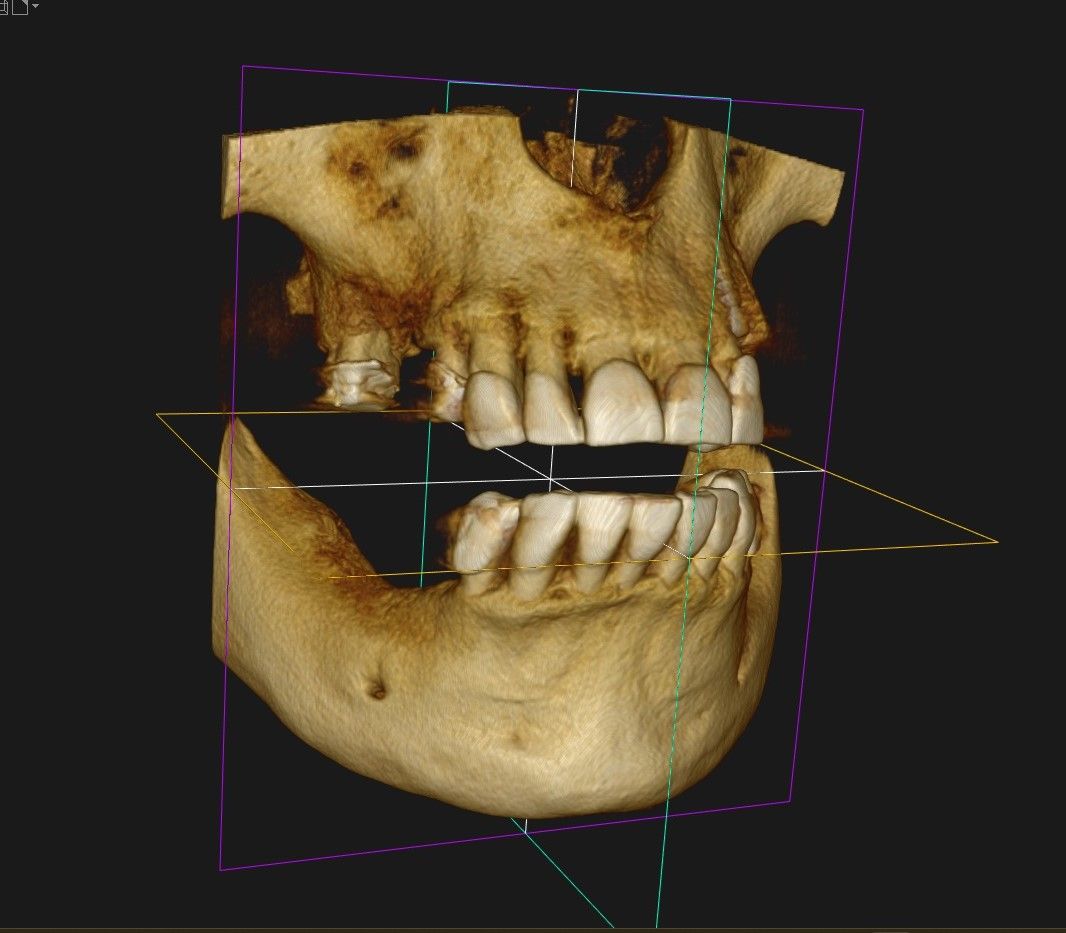

Presso il nostro Studio Dentistico, ci occupiamo di una vasta gamma di specializzazioni, tra cui Endodonzia, Pedodonzia, Ortodonzia, Gnatologia, Chirurgia Orale, Implantologia, Protesi Fissa e Mobile. La nostra esperienza si estende anche a trattamenti di Igiene Orale, Odontoiatria Generale, Parodontologia, Estetica Dentale con Sbiancamento, Medicina Estetica del Viso, il tutto avvalendoci di tecnologie avanzate per garantire risultati ottimali e duraturi.